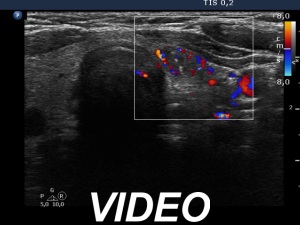

Ultrasonography. The thyroid was echonormal. Beside several hypoechoic and cystic lesions without any clinical significance, both lobes had a hypoechoic nodule. The presentation of them was very similar, both had echogenic granules and showed peripheral vascularity. However, the echogenic figures in the right nodule were probably back wall figures while those in the left nodule were microcalcifications. Regarding the vascularity, the left nodule showed perinodular blood flow while the right did not.